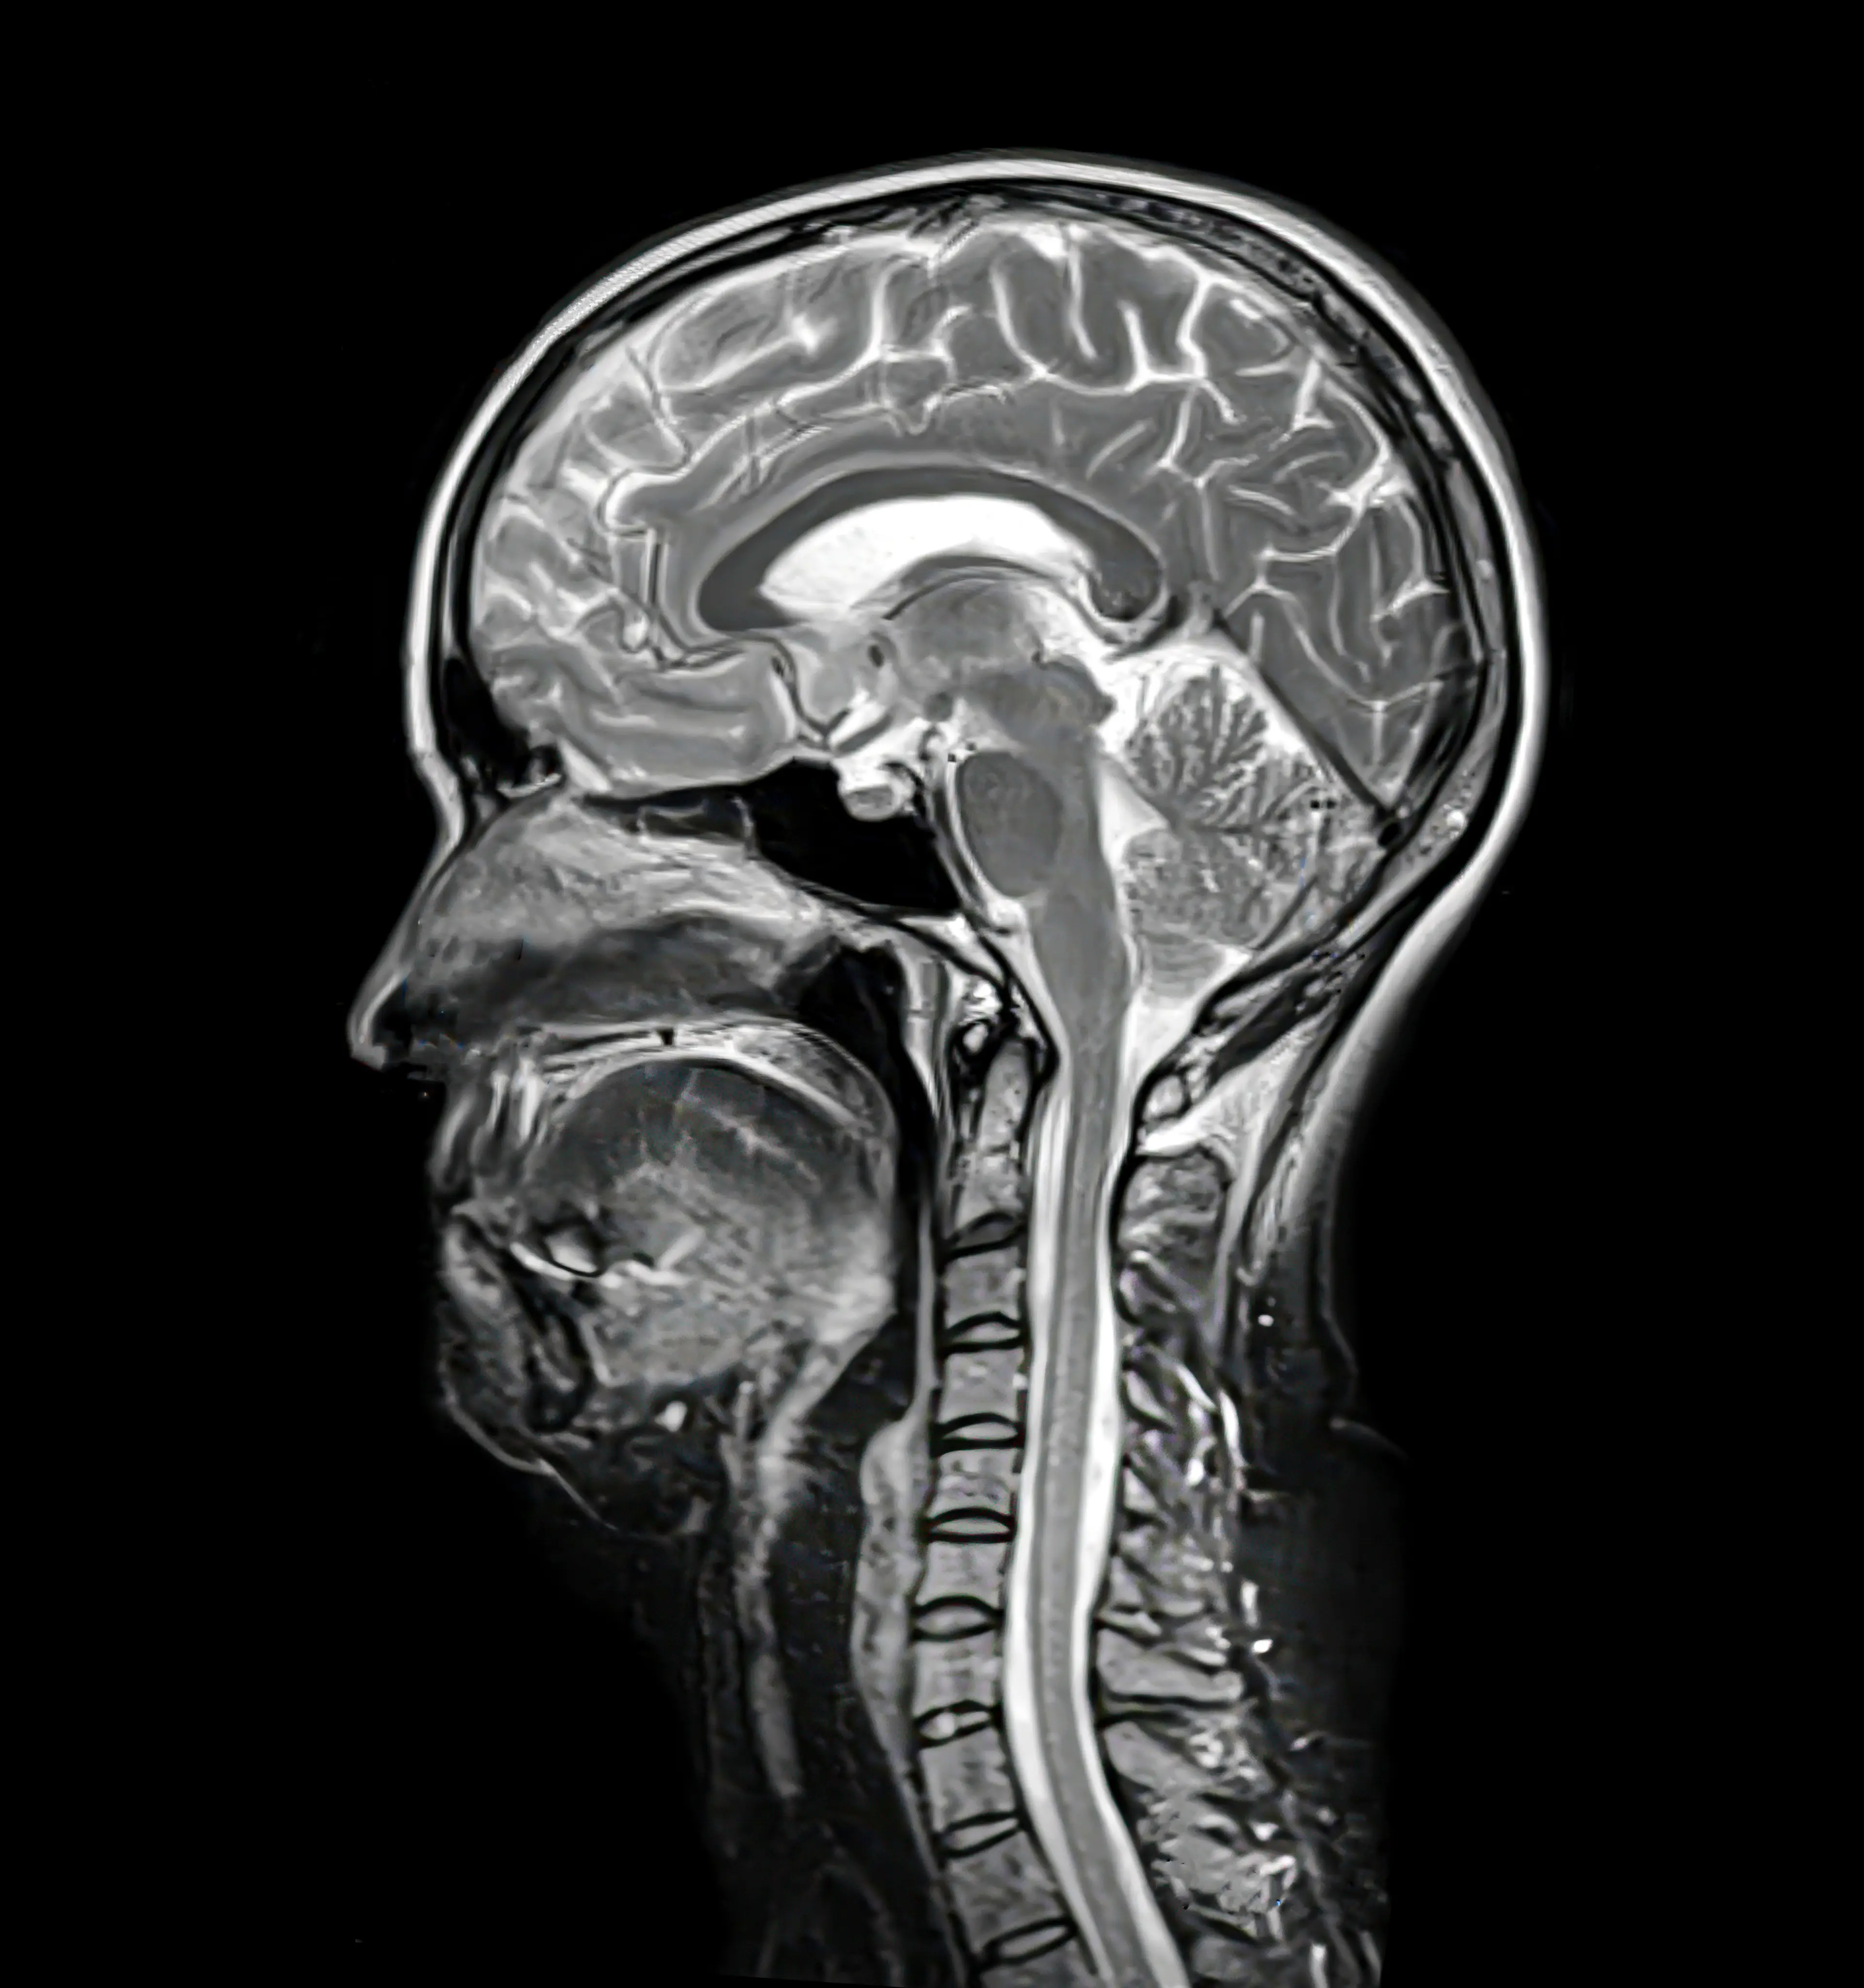

Dr Bing warned: "Taking too high doses of vitamin D can cause calcium to build up in your blood, which can affect the brain, leading to things like confusion, fatigue, depression, and sometimes even psychosis.

"Too much of this can lead to a condition called pseudotumor cerebri, which is increased pressure in the brain that mimics a brain tumour, causing headaches, blurred vision and even permanent vision loss."

"Copper is essential for your nervous system. And low copper levels can cause something called myeloneuropathy, which is damage to the spinal cord and your peripheral nerves, leading to things like numbness, tingling and trouble walking.